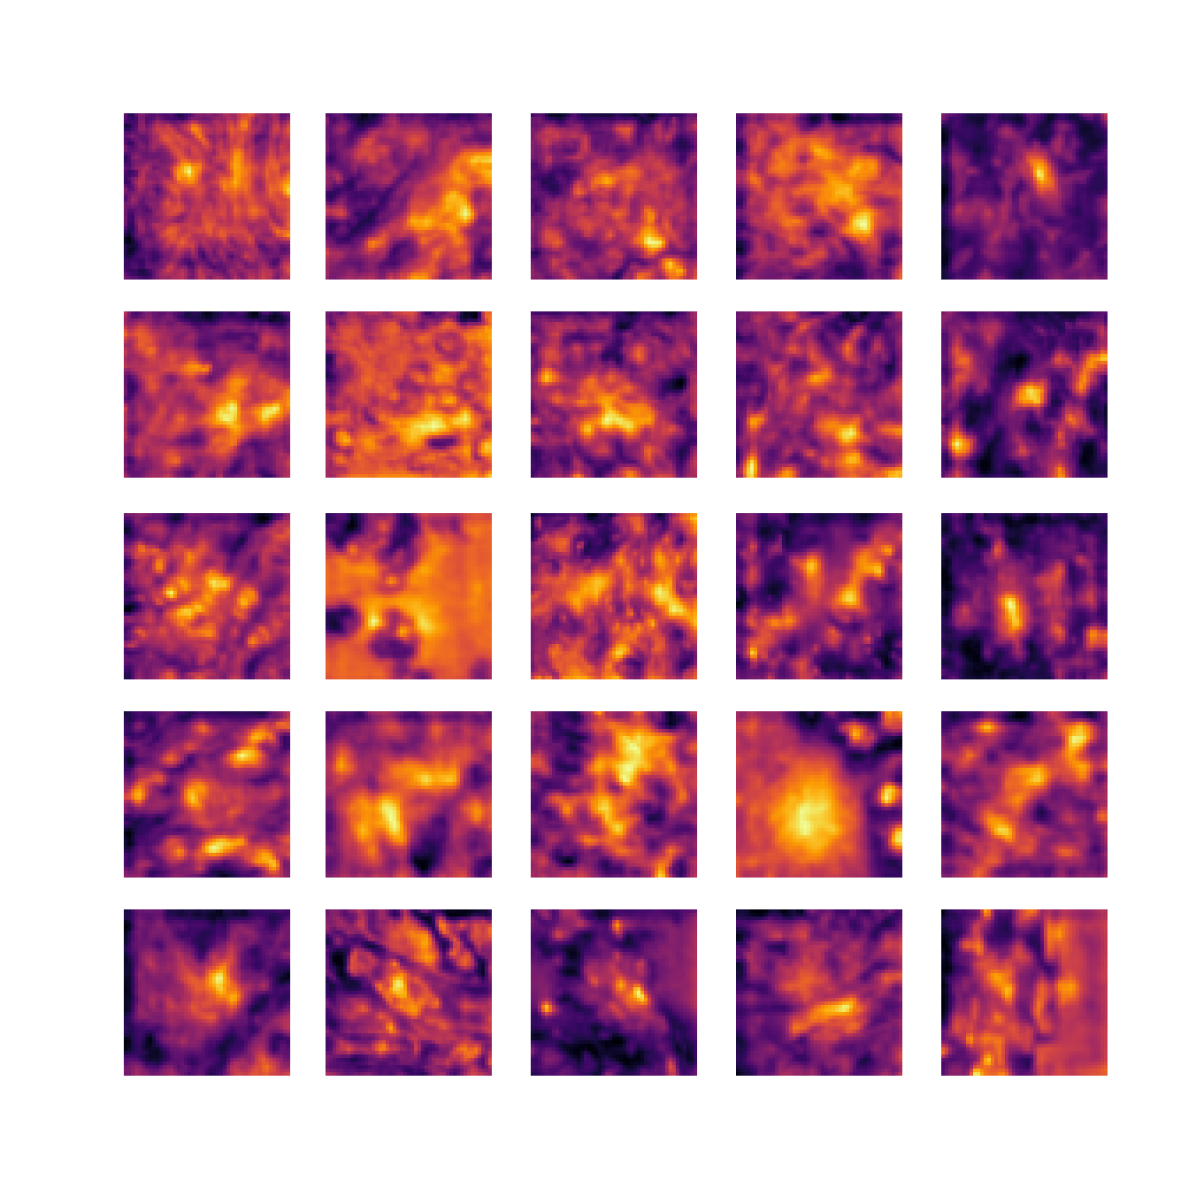

We also analyse the activation maps for each model using GradCAM as described in section S3. This offers more insight into the areas of the image which are contributing most heavily to the models’ representations. In Figure 4(b) we present some representative examples, however, a larger selection which was chosen at random is presented in Figures S10 to S25. The larger selection makes it easier to see the emergent patterns, including that privileged Siamese models tend to mainly identify features which are strongly present in both inputs, while unprivileged Siamese models tend to learn more diffuse features that are not specific to one cell phenotype or image region. TriDeNT ♆ incorporates both sets of features, learning both features specific to the privileged data and more the general features associated with unprivileged Siamese networks.

We can see in Figure 4(b) panel A that for ERG, the privileged Siamese model focuses almost exclusively on any nuclei which could be endothelial cells. As there are very few endothelial cells in the dataset, it could be an effective strategy to identify anything that could potentially be an endothelial cell to minimise the difference between the representations of the H&E model and the IF mask model. In the corresponding unprivileged Siamese image, we see that the model identifies some of these nuclei, albeit less strongly, but also focuses heavily on the other tissue and even the background, while strongly fixating on two spots of debris in the center of the image. This model has less ‘incentive’ to learn the weak features related to endothelial cells as these occur rarely and are not easy to detect, while more generic strong features such as the presence of connective tissue and the prevalence of background are more common and predictable from augmented images. We see that TriDeNT ♆ combines these two feature sets, strongly identifying nuclei while also identifying the connective tissue.

In panel C we see a similar pattern, with the privileged Siamese model fixating solely on the nuclei, while the TriDeNT ♆ model takes a more balanced approach. The unprivileged Siamese model appears to focus on a single cluster of nuclei while neglecting others, and similarly identifies an area of fibroblasts with its distinctive pattern but does not others.

In contrast to panels A and C which represent models with poor privileged Siamese results, panels B and D represent models whose privileged Siamese results were comparable to both TriDeNT ♆ and even the supervised baseline. It is therefore interesting to note that there are far more similarities between the privileged Siamese and TriDeNT ♆ models in both cases. Particularly in panel B, TriDeNT ♆ and the privileged Siamese model return virtually identical heatmaps, with both strongly identifying epithelial nuclei and neglecting the same areas of connective tissue. The unprivileged model in this case appears to focus solely on the centre of the image, giving a significantly different heatmap to the other panels.

Panel D again shows the previous pattern, with the privileged Siamese model identifying the features strongly present in the privileged data – fibroblasts – while neglecting the nuclei present. TriDeNT ♆ also strongly identifies the connective tissue, but, unlike the privileged Siamese model, does not completely neglect the nuclei. The unprivileged Siamese model primarily identifies background, and does not appear to identify the nuclei in this example.